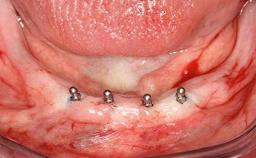

Improving an Existing Implant-supported Denture in an Alzheimer Patient with Bipolar Affective Disorder with Moderate Depression and Dementia

An 83-year-old man presented together with his caregiver at the dental department of the Medical University of Innsbruck, Austria with complaints of swelling in the right maxillary canine area and loss of retention of his 5-years-old mandibular denture. The patient had a significant medical history (20 years) of bipolar affective disorder with moderate depression (F 31.3) and dementia in Alzheimer’s disease (F 00.2). The patient had been in ambulant psychiatric therapy for his depressive illness for the past 20 years. He lived alone and had no children; his sister assisted with daily living. She reported that the patient exhibited compulsive hoarding behavior. In the previous two months, she had noted increasing disorientation and vertigo in the patient. She therefore accompanied him for a medical consultation at the Department of Psychiatry and Psychotherapy of the Medical University of Innsbruck. He was released home after a 6-week inpatient stay.

# of Implants 2

Type of Implants One-Piece

Attachment One-Piece

Defining Characteristics Fully edentulous lower jaw to be rehabilitated with two or more implants

Modality 2 interforaminal implants